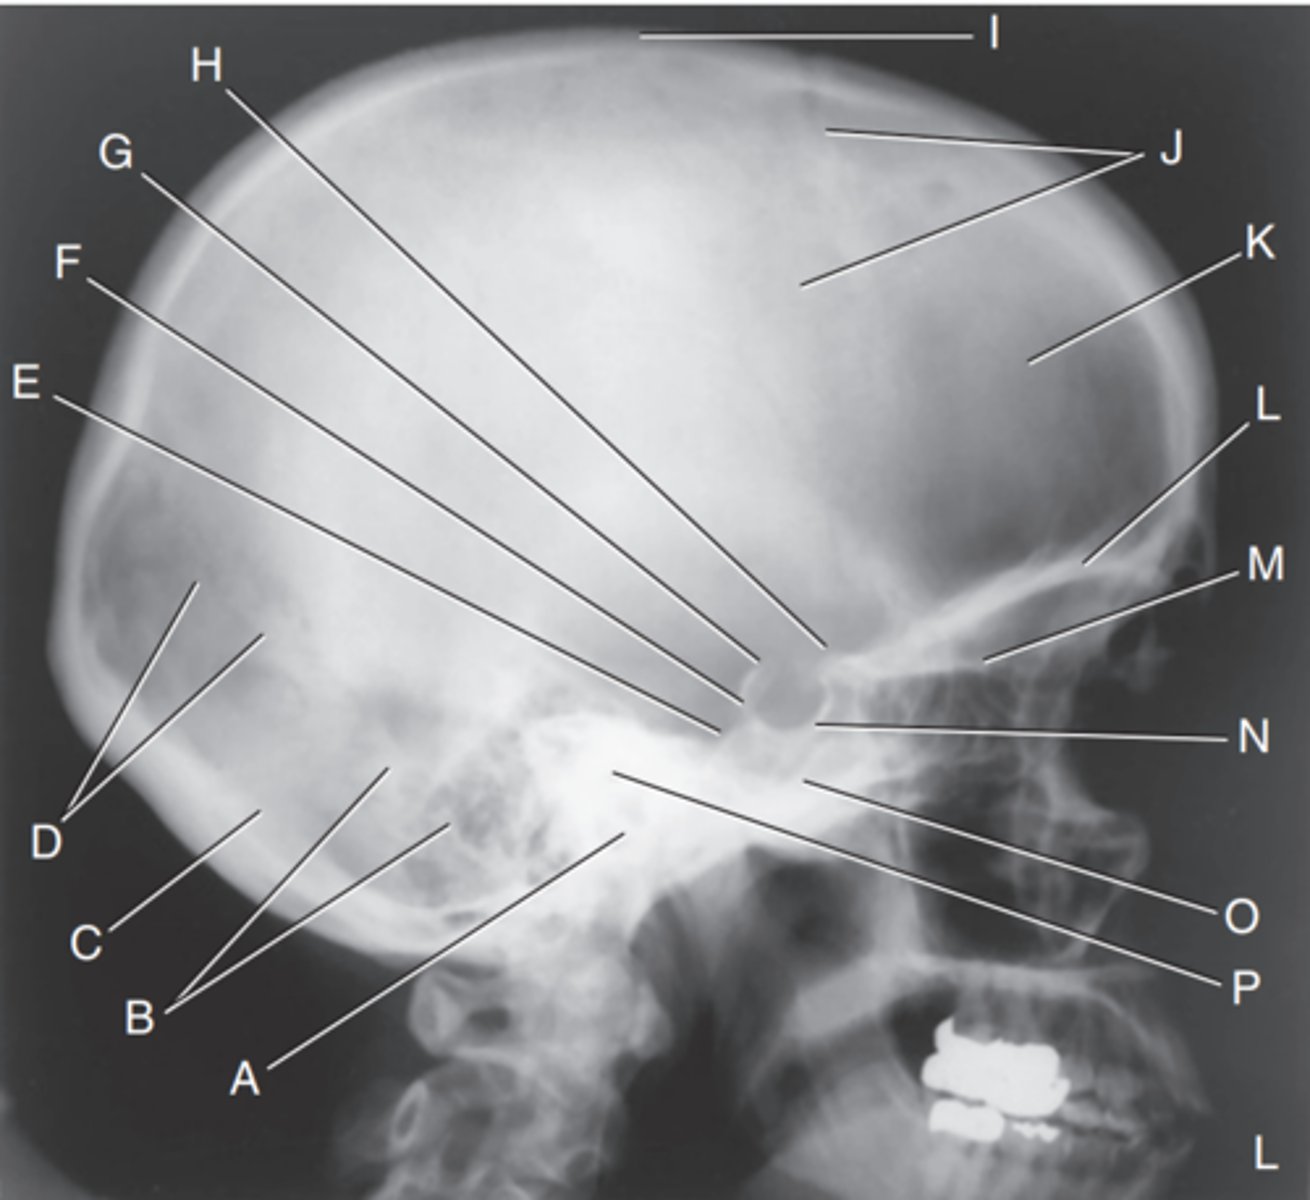

EAM

Label A

Mastoid portion of temporal bone

Label B

Occipital bone

Label C

Lambdoidal suture

Label D

Clivus

Label E

Dorsum sellae

Label F

Posterior clinoid processes

Label G

Anterior clinoid processes

Label H

Vertex of cranium

Label I

Coronal suture

Label J

Frontal bone

Label K

Orbital plates

label L

Cribriform plate

Label M

Sella turcica

Label N

Body of sphenoid (sphenoid sinus)

Label O

Petrous portion of temporal bone

Label P